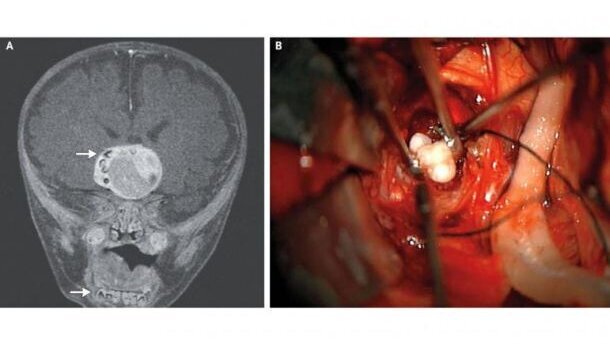

MARYLAND, VS – Bij een vier maanden oude Amerikaanse baby is een hersentumor met tanden verwijderd. De baby had een zeer zeldzame, langzaam groeiende tumor in de hersenen. Toen de artsen de tumor verwijderden, vonden ze een aantal volgroeide tanden in het tumorweefsel, zo beschrijven zij in het New England Journal of Medicine.

Bij routinecontroles op het consultatiebureau bleek de hoofdomtrek van de baby te snel te groeien. Op een MRI zagen artsen een heterogene massa van ongeveer 4 cm in doorsnede. Aan de zijkant van de massa waren een aantal structuren zichtbaar die gelijkenis vertoonden met tanden in een kaakbot.

De tumor werd operatief verwijderd, waarbij de artsen inderdaad een aantal volledig ontwikkelde tanden in de tumormassa aantroffen. Pathologisch onderzoek wees uit dat het om een adamantinomateus craniopharyngioom ging. Dit is een langzaam groeiende tumor die ontstaat uit de embryologische structuur waaruit de hypofyse ontstaat. De zeer zeldzame tumor verspreidt zich niet en kan zo groot worden als een golfbal. Histologisch vertonen deze tumoren veel gelijkenis met odontogene tumoren en cysten.

Aangezien de tumor uit het hypofyseweefsel groeide, is bij de operatie een deel hiervan weggenomen. De baby ontvangt daarom nu hormoontherapie om zijn schildklier en bijnieren nog goed te laten functioneren. Volgens de artsen verloopt zijn ontwikkeling in het eerste jaar na de operatie normaal. De gezondheid van de baby wordt met regelmatige MRI-scans gevolgd.